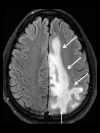

Toxic leukoencephalopathy results from damage to the white matter caused by various toxins. It manifests itself as white matter signal abnormalities with or without the presence of restricted diffusion. These changes are often reversible if the insulting agent is removed early, with the exception of posthypoxic leukoencephalopathy that can manifest itself 1-2 weeks after the initial insult. However, many other potential causes of white matter signal abnormalities can mimic the changes of toxic leukoencephalopathy. Thus, familiarity with the causes, clinical presentation and particularly imaging findings of toxic leukoencephalopathy is critical for early treatment and improved prognosis. The purpose of this pictorial essay is to familiarize the reader with the various causes of toxic leukoencephalopathy along with its differential diagnoses and mimics.